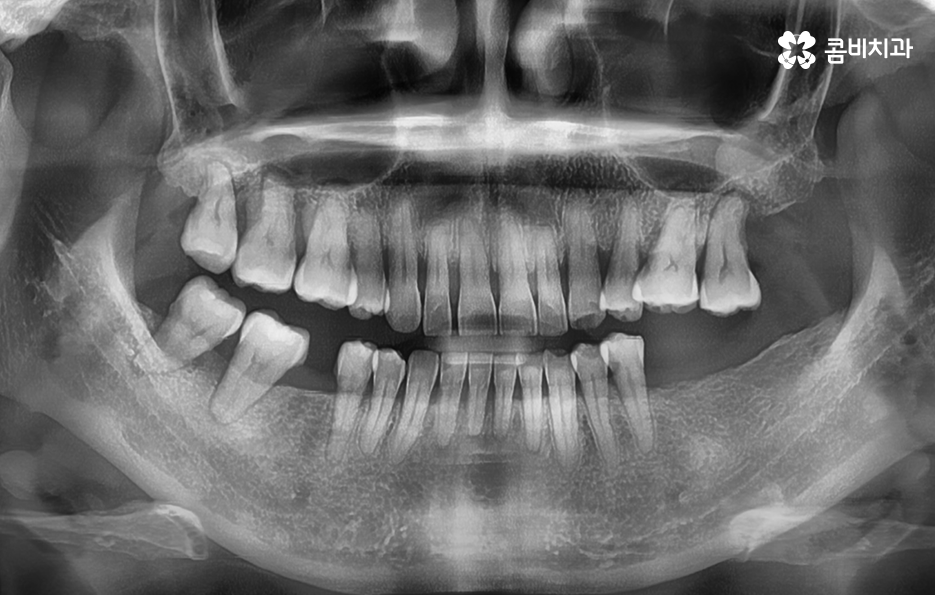

오늘 보시는 포스팅에서의 치료 과정도 어금니에 임플란트가 필요한 상태에서 윗니를 보시면 윗니가 다소 벌어진 것을 확인할 수 있는데요. 교정 하면 보통 전체교정을 떠올리게 되긴 하지만 경우에 따라서는 치열이 전체적으로 가지런한 편인데 앞니가 살짝 벌어진 경우나 어금니만 다소 벌어진 경우도 있을 거예요

이러한 경우에는 부분교정을 통해서 다소 개선이 필요한 치열을 가지런하게 만들고 가지런해진 치열과 교합 상태에 적합한 임플란트 치료 계획을 세워서 치아의 심미성과 기능적인 부분, 얼굴과의 조화를 종합적으로 고려하여 좋은 결과를 얻을 수 있어요